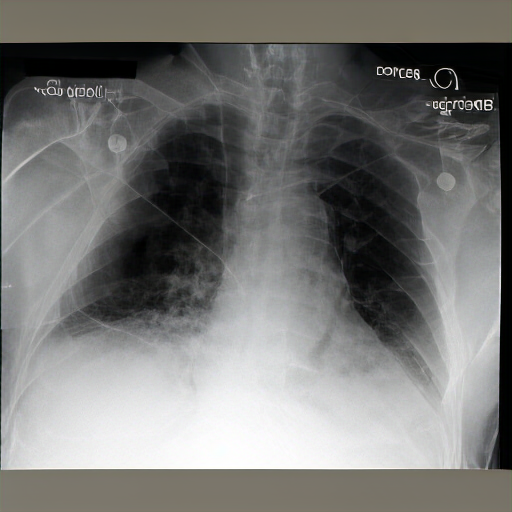

There are moderate-to-severe vascular congestion as well as perihilar opacification on the left than on the right. There is indistinctness of pulmonary vessels, suggestive of small-to-moderate pulmonary edema. There is no pneumomediastinum, a new small-to-moderate right-sided pleural effusion has not changed allowing for somewhat. There is no definite pneumothorax. A dialysis catheter has been removed.

Severe cardiomegaly is present. Previous mediastinal widening has improved. A region of consolidation, more discrete at the right base and in the left lower lobe, presumably with long-standing infection, is noted. There is increased vascular engorgement. No pulmonary edema is seen. Mediastinal vascular engorgement is present. A dual-channel hemodialysis catheter is at the cavoatrial junction, and atrial node tubes are in place.

The lungs are well expanded and appear clear. Cardiomediastinal silhouette and hilar contours are otherwise unremarkable. No pleural effusion, or pneumonia pneumothorax. IMPRESSION: No acute cardiopulmonary process or evidence of traumatic injury or acute aortic abnormality are. Consider CT to be in etiology and sensitivity for fractures.